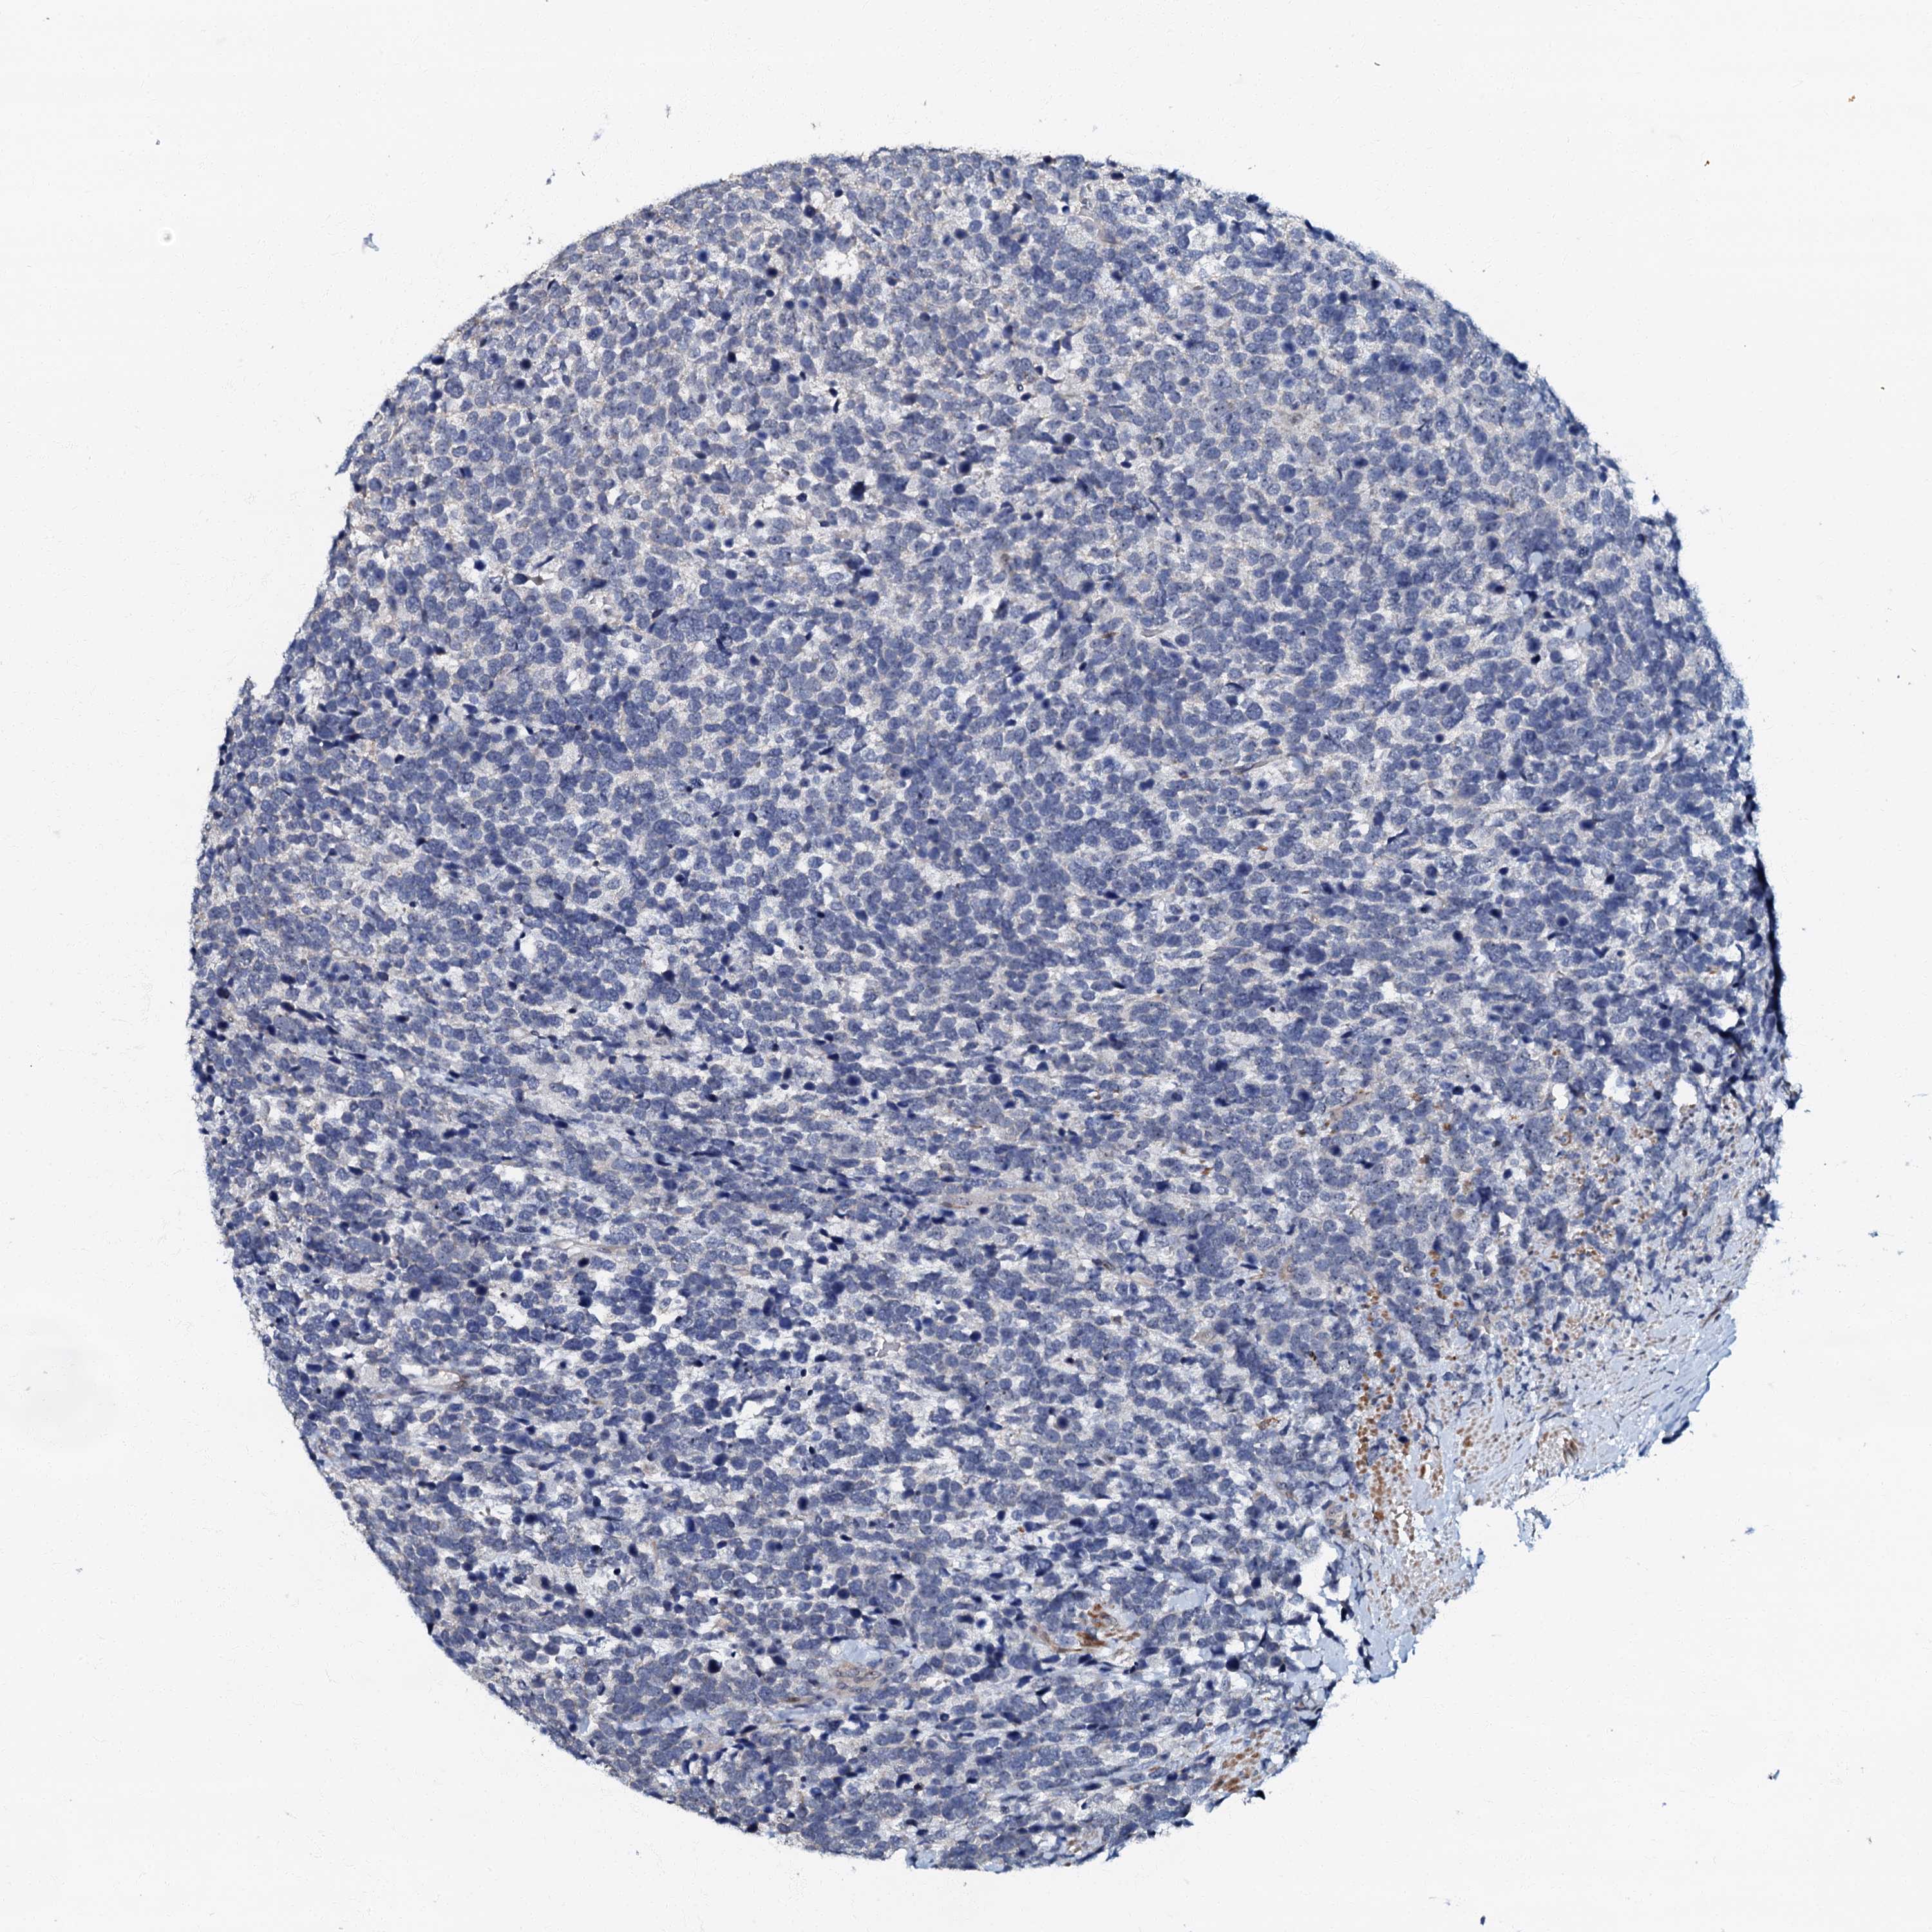

UROTHELIAL CANCER - Protein expressioni

A mouse-over function shows sample information and annotation data. Click on an image to view it in a full screen mode. Samples can be filtered based on level of antibody staining by selecting one or several of the following categories: high, medium, low and not detected. The assay and annotation is described here.

Antibody stainingi

Antibody staining in the annotated cell types in the current human tissue is reported as not detected, low, medium, or high, based on conventional immunohistochemistry profiling in selected tissues. This score is based on the combination of the staining intensity and fraction of stained cells.

Each image is clickable and will lead to virtual microscopy that enables deeper exploration of all samples and also displays staining intensity scores, fraction scores and subcellular localization as well as patient and tissue information for each sample.

Antibody HPA037947

Antibody HPA037948

Staining

High

Medium

Low

Not detected

Intensity

Strong

Moderate

Weak

Negative

Quantity

>75%

75%-25%

<25%

None

Location

Nuclear

Cytoplasmic/membranous

Cytoplasmic/membranous,nuclear

Urothelial carcinoma, High grade

Urothelial carcinoma, Low grade

Urothelial carcinoma, NOS